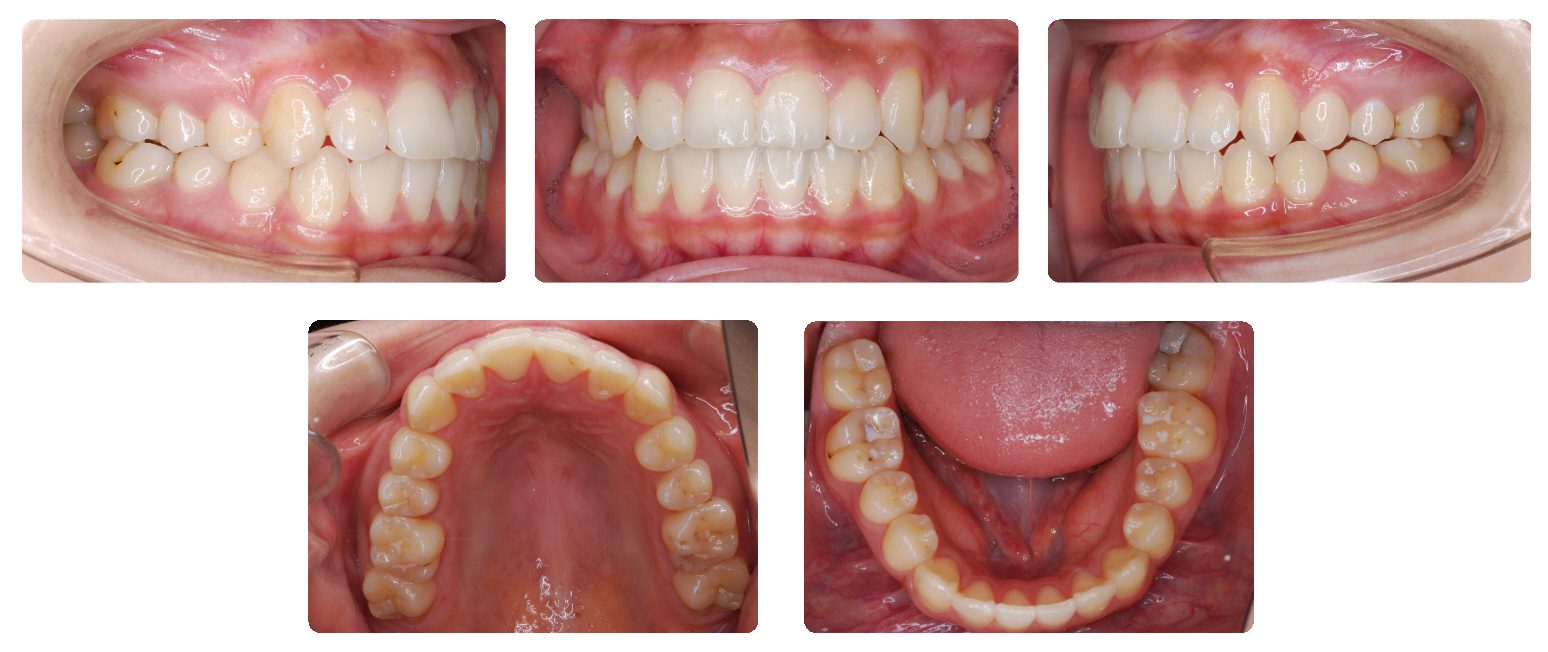

動的治療期間は4年でした。

治療途中で服用薬の副作用による歯肉腫脹の状態を考慮して、動的処置の最終仕上げの前でところどころに至らない箇所がありますがいったん上下顎の装置を外して保定に移行しました。

保定期間が8か月ほど終了した後に、取り外しのできるマウスピースによる矯正治療で歯並びの仕上げを行いました。仕上げの動的処置期間は約2か月でした。